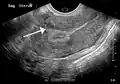

Diagnosis

Physical examination and ultrasound are sufficient for diagnosing uterine fibroids in the majority of people. When ultrasound findings are inconclusive, magnetic resonance imaging (MRI) may be able to confirm the diagnosis of uterine fibroids in most cases. In addition, MRI can identify benign uterine fibroids with atypical imaging features and fibroids with variant growth patterns. MRI can also identify other uterine (e.g. adenomyosis, endometrial polyps, endometrial cancer) and extrauterine (e.g. benign and malignant ovarian tumors, endometriosis) disorders that may mimic the appearance of uterine fibroids and/or contribute to the patient's symptoms.[38] However, a small proportion of uterine fibroids can mimic other malignant uterine tumors (e.g. leiomyosarcoma) on all available imaging modalities (e.g. ultrasound, CT, MRI and PET-CT).[38]

Malignant tumors of the uterine wall (e.g. leiomyosarcoma) are very rare. Findings suggestive of a malignant uterine tumor rather than a benign fibroid include, fast or unexpected growth (particularly after menopause), interruption/effacement of the endometrial stripe, lymph node enlargement, invasion of adjacent organs and metastases to distant organs (e.g. lung). MRI findings suggestive of a malignancy include nodular/ill-circumscribed tumor margins, intermediate/high T2-weighted signal intensity of the solid tumor components, regions with high signal T1-weighted sequences in keeping with subacute hemorrhage, fine/wispy enhancement of the solid parts of the tumor, and restricted diffusion on diffusion-weighted imaging (DWI).[38] A biopsy is rarely performed and if performed, is rarely diagnostic. Should there be an uncertain diagnosis after ultrasounds and MRI imaging, surgery is generally indicated.[39]